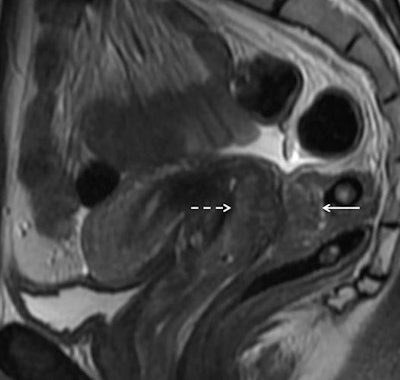

A 34-year-old woman with dyspareunia and dyschezia. This sagittal T2-weighted image through the pelvis reveals a large endometriotic deposit within the rectovaginal septum. The mass has an "hourglass" configuration and is infiltrating the posterior vaginal fornix anteriorly (dashed arrow) and the rectal muscularis posteriorly (solid arrow). The nodule represents fibromuscular hyperplasia around ectopic endometrial glands. There is commonly preservation of the overlying rectal mucosa, seen as a high signal intensity (bright) line overlying the mass. Endometriotic infiltration of the muscle dictates a different surgical approach than the presence of adhesions or serosal involvement alone. Image courtesy of Dr. Susan Freeman.Urinary tract endometriosis is quite rare, but where it does occur, it is often seen as serosal plaques and deposits on the bladder. Ureteral involvement can also arise, and this may lead to hydronephrosis. Sometimes it is difficult to see parametrial disease, but careful scrutiny may reveal medialization of the ureter, she continued.